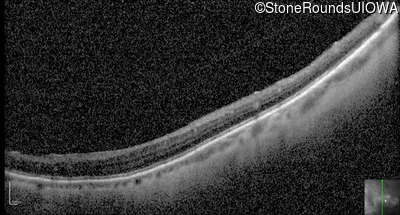

Optical Coherence Tomography - Left - 20/50 +3

Exemplar / OCT Stack

OCT Stack